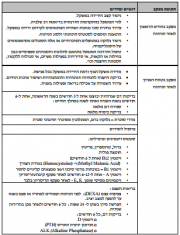

| 16:57, 29 בפברואר 2016 | Cdt2.png (קובץ) |  |

826 קילו־בייטים | Motyk | 1 | |

| 22:24, 28 בפברואר 2016 | Cdt1.png (קובץ) |  |

531 קילו־בייטים | Motyk | 1 | |